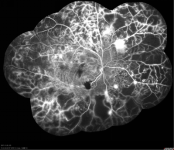

糖尿病患者一旦血糖控制不穩(wěn)定,引起眼睛發(fā)生病變,造成糖尿病視網(wǎng)膜病變,導(dǎo)致視物模糊等不適癥狀,需要來(lái)院就診。除了眼科常規(guī)檢查,眼底血管造影也是為醫(yī)生的診斷和后續(xù)治療提供相關(guān)依據(jù)的有力檢查項(xiàng)目。

(眼底血管造影檢查能清楚準(zhǔn)確地展示出糖尿病視網(wǎng)膜病變的程度和進(jìn)展)